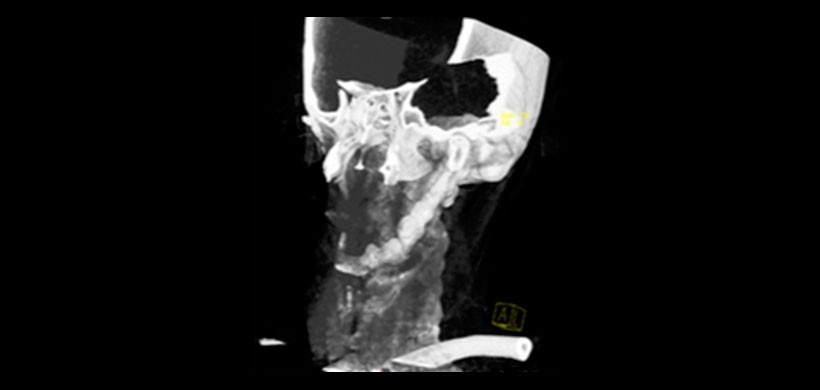

Se han utilizado múltiples modalidades de estudio imagenológico para confirmar el diagnóstico clínico, incluyendo las radiografías lateral de cuello y anteroposterior de cráneo, panorármica, la tomografia computarizada de haz cónico (TCHC) y la tomografía espiral multicorte (TEM) La técnica de elección para el diagnóstico y evaluación del síndrome de Eagle es el TEM con reconstrucción 3D. Permite obtener información del tamaño, dirección y relación del complejo estiloideo con las estructuras vasculonerviosas cercanas

Figura 3: Renderizado de la tomografía de haz cónico, muestra de manera grafica la mineralización, el cual se le puede mostrar al paciente de manera didactica para proceder con el tratamiento de elección.